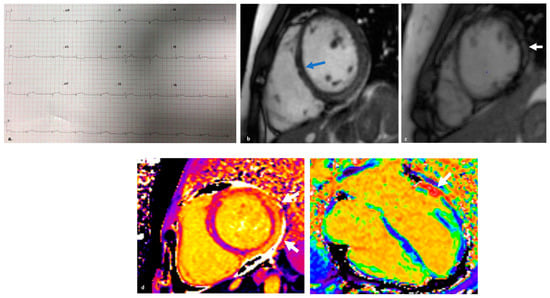

5. Arrhythmogenic Right Ventricular Cardiomyopathy with “Hot Phase” Episodes

5.2. Clinical Findings and Genetics

5.3. Diagnostics